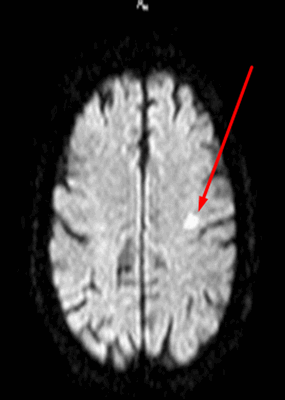

Очаги ишемии на МРТ

Очаги ишемии

Нарушения мозгового кровообращения приводят к кислородному голоданию тканей, что может спровоцировать их некроз (инфаркт). Ишемические очаги при Т2 взвешенных последовательностях выглядят как зоны с умеренно гиперинтенсивным сигналом неправильной формы. На более поздних сроках при проведении в Т2 ВИ или FLAIR режиме МРТ единичный очаг приобретает вид светлого пятна, что указывает на усугубление деструктивных процессов.